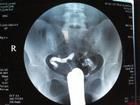

粘堵術後X線所見

1.粘堵術成功的X線征

(1)雙側輸卵管顯影,其長度為4厘米,為較理想的充盈,粘堵藥物主要作用在輸卵管間質部及峽部,破壞管壁黏膜,促進肉芽增生,達到絕育目的。

(2)雙側輸卵管充盈達壺腹部,藥物在輸卵管內充盈越長,則管腔阻塞段也相應較長。

(3)雙側輸卵管充盈超過1.5厘米。

(4)如宮角處有粘堵劑充盈,雖然輸卵管只充盈1厘米,也可達避孕效果。

但為安全起見,最好做術後子宮造影,觀察輸卵管阻塞情況,如輸卵管粘堵成功,X光片中顯示宮角圓鈍。間質部一般均不顯影,只有少數間質部有不同程度的顯影。因間質部是輸卵管最細一段,黏膜平坦,肌層厚,血管豐富、是最容易產生阻塞部位。

2.粘堵術失敗的X線征

(1)輸卵管不顯影表示粘堵失敗,有時一側輸卵管顯影,另一側輸卵管未顯影也屬失敗。

(2)輸卵管充盈短於1.5厘米者。

(3)造影劑進入宮角血管 造影劑進入宮角黏膜下小靜脈,X片顯示網狀陰影。

(4)造影劑進入宮角肌層 多見於哺乳期,子宮軟易插到肌層,或由於反覆插管,宮角附近黏膜受傷,X片。